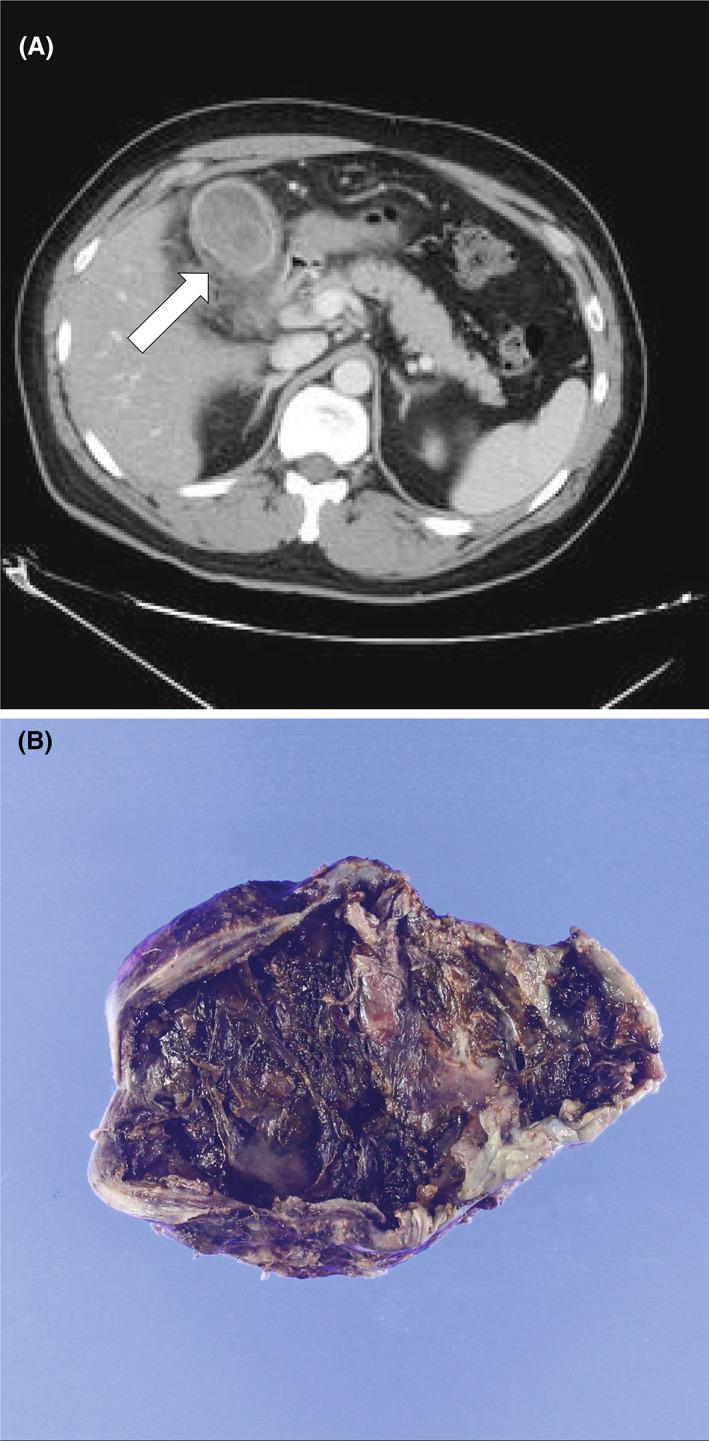

Diagnosing gangrenous cholecystitis on computed tomography using deep learning: A preliminary study.

To compare deep learning and experienced physicians in diagnosing gangrenous cholecystitis using computed tomography images and explore the feasibility of diagnostic assistance for acute cholecystitis requiring emergency surgery.

This retrospective study included 25 patients with pathologically confirmed gangrenous cholecystitis and 129 patients with noncomplicated acute cholecystitis who underwent computed tomography between 2016 and 2021 at two institutions. All available computed tomography images at the time of the initial diagnosis were used for the analysis. A deep learning model based on a convolutional neural network was trained using 1,517 images of 112 patients (18 patients with gangrenous cholecystitis and 94 patients with acute cholecystitis) and tested with 68 images of 42 patients (seven patients with gangrenous cholecystitis and 35 patients with acute cholecystitis). Three blinded, experienced physicians independently interpreted the test images. The sensitivity, specificity, accuracy, and area under the receiver operating characteristic curve were compared between the convolutional neural network and the reviewers.